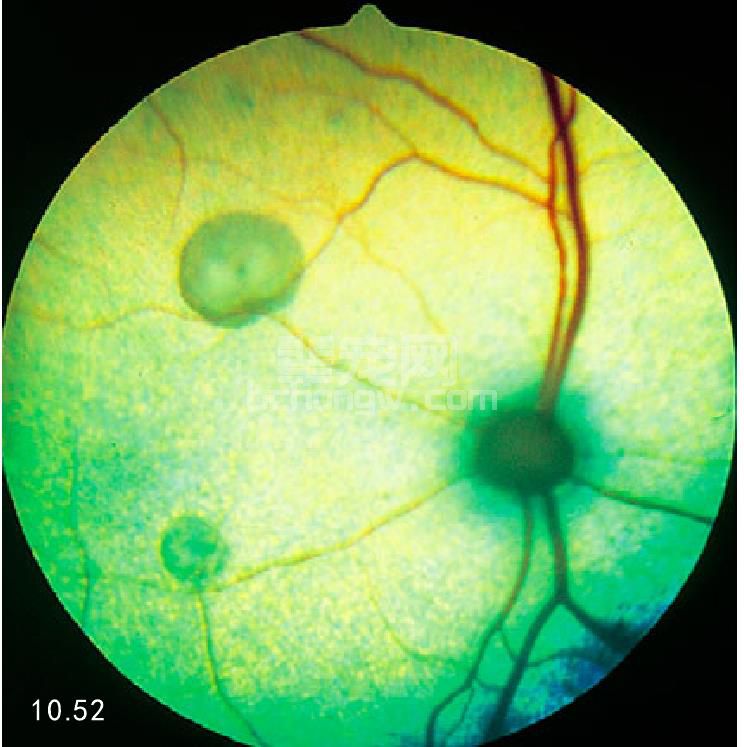

临床症状 视网膜或脉络膜视网膜炎症的症状包括:水肿、炎性细胞浸润和形成肉芽肿、出血及存在渗出性 视网膜脱落的可能(图10.52和图10.53)。犬视网膜渗出、出血、脱落是本病的后续症状(图10.54)。

图10.52 猫的非活动性脉络膜视网膜炎分界明显 的病灶区